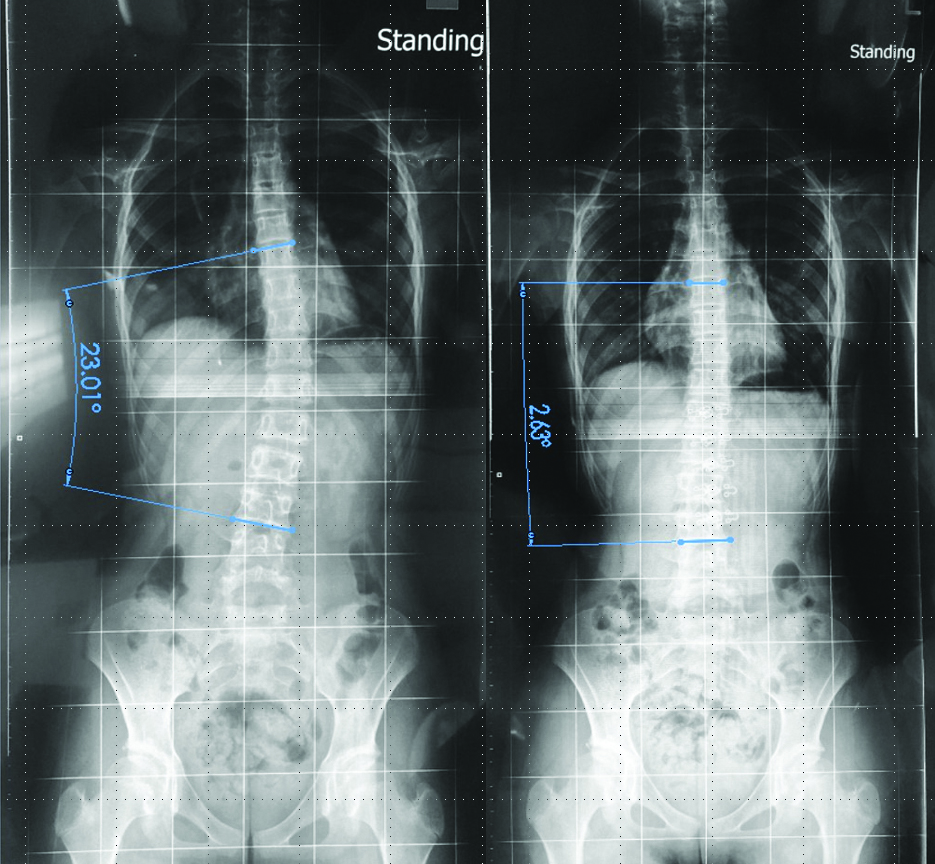

The innovative scoliotic brace is a functional garment specially designed for adolescents with scoliosis. The shape memory alloy (SMA) and the artificial hinges used in this design apply strategic corrective forces to the spine, providing adequate support to the wearers. Combining clinical practice, materials science and textile technology, the scoliotic brace of high wearing comfort can control the progression of spinal deformities more effectively and improve patient compliance, thus reducing the possible need for orthotic interventions or surgery.